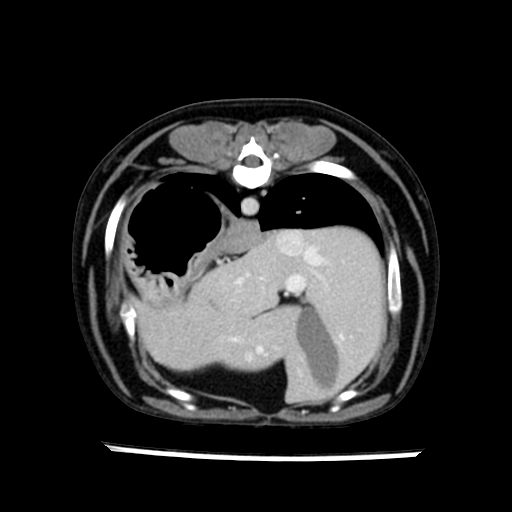

prescritto esame TAC

sequenza immagini limitata al fegato reni e surreni

sospetto adenoma ipofisario vs. meno probabilmente meningioma della base; intertiziopatia polmonare; lesione espansiva epatica, verosimilmente del lobo laterale sinistro, di sospetta natura neoplastica; lesioni spleniche di natura da definire; iperplasia/ipertrofia delle ghiandole surrenali, bilateralmente; vertebra di transizione del rachide toracico; tenosinovite cronica del muscolo bicipite brachiale di destra.

- Nessuna informazione diversa per quello che riguarda l’esame ecografico del fegato e la presa del contrasto si confermano le lesioni individuate e l’ipoenanchement in fase portale.